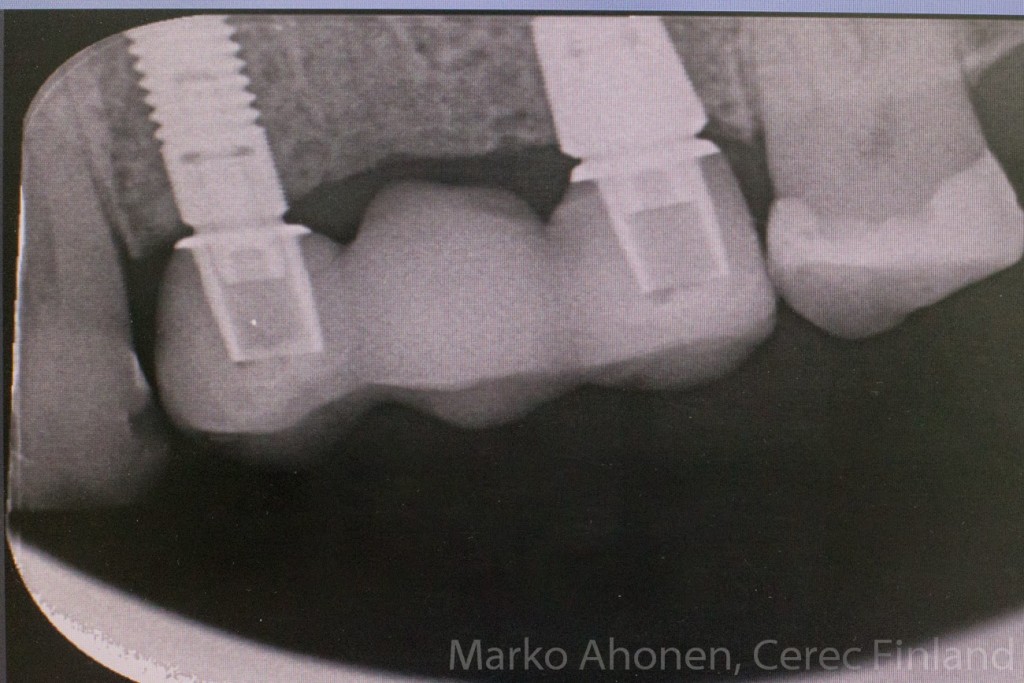

Lopullinen röntgenkuva näyttää erittäin hyvän istuvuuden jatkeille ja sementoitavalle sillalle:

IMG_4526